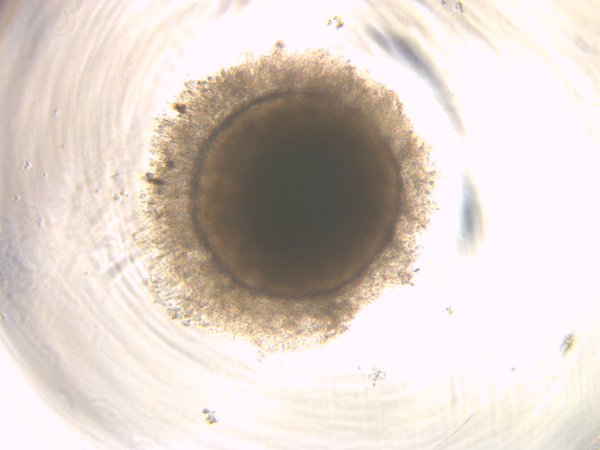

Wildtype (wt2D)

wt2D

Healthy control, Day 10